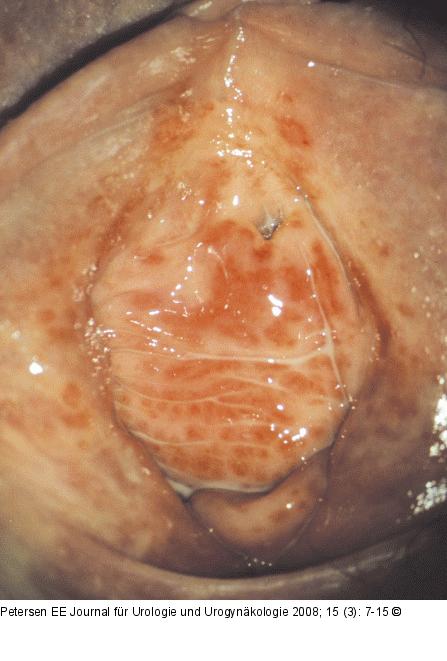

Abbildung 6: Vulvitis - Kolpitis Vulvitis und Kolpitis plasmacellularis, 42 Jahre. |

Vulvitis und Kolpitis plasmacellularis, 42 Jahre. |